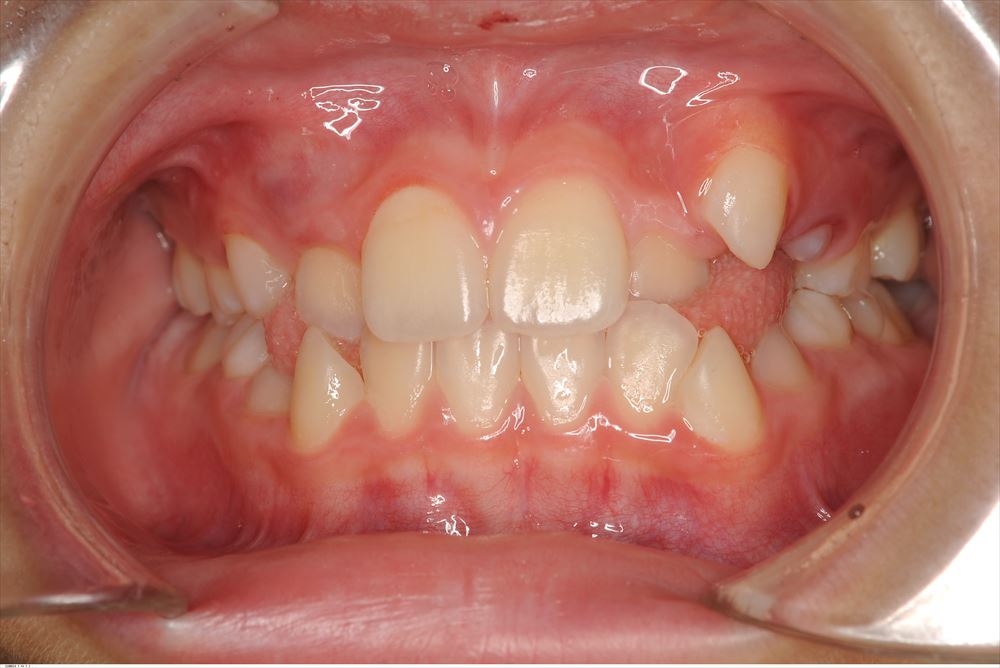

今日は矯正の装置を外した女の子。外してとても喜んで頂けました。

術前。あらま。

今日

リテーナー使ってねー。